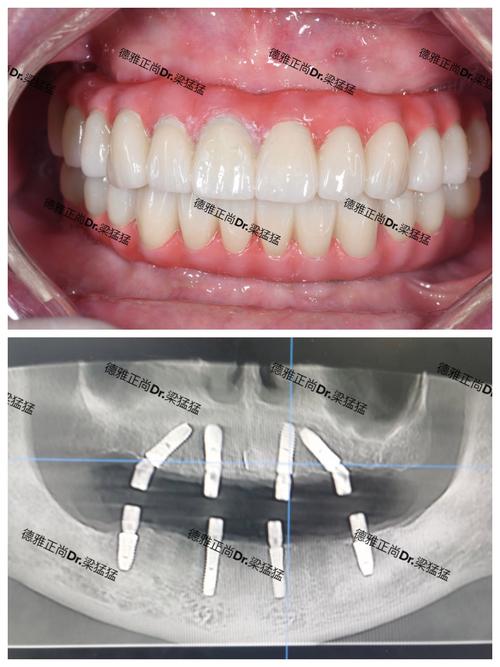

(图片来源网络,侵删)- 私立诊所或高端专科医院通常服务流程更人性化,预约更灵活,环境更舒适,注重患者体验。